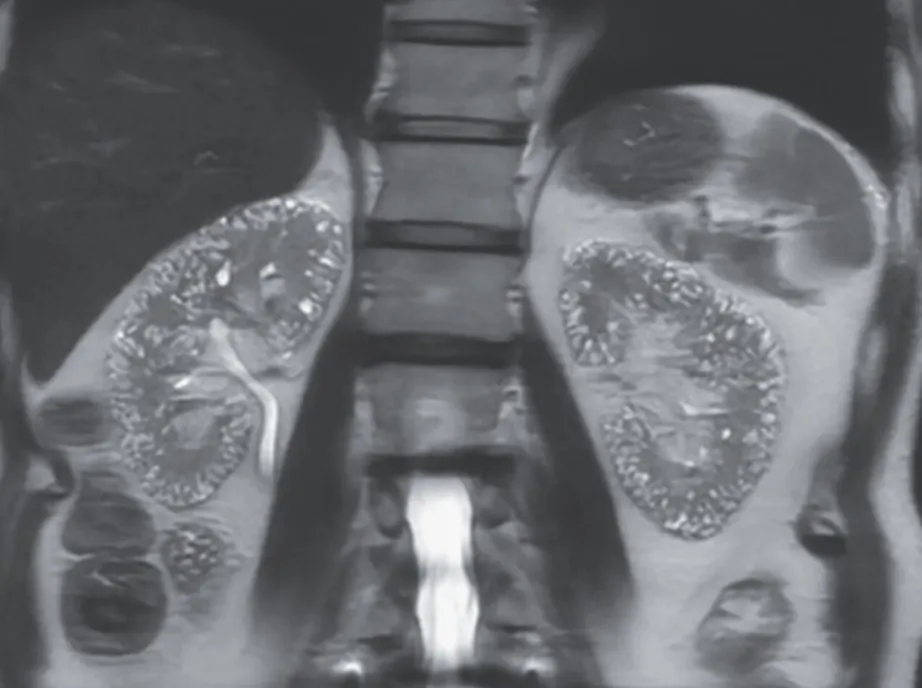

Uma tomografia computadorizada (TC) contrastada revelou focos corticais hipoatenuantes mal definidos e um aumento do volume renal (imagem abaixo).

2. A TC com contraste pode revelar áreas de baixa densidade nos rins